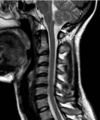

foramen magnum

40

4th ventricle

41

right head of caudate nucleus

42

greater wing of right sphenoid

43

left cerebello pontine angle

44

interpeduncular cistern

45

choroid plexus of left lateral ventricle

46

C3/4 facet joint

47

pituitary stalk

48

left mandibular canal

49

right foramen ovale

50

right condylar process of mandible

51

right infraorbital canal

52

nasal septum

53

left lateral pterygoid muscle

54

4th ventricle

55

ethmoid sinus

56

medulla oblongata

57

clivus

58

anterior communicating artery

59